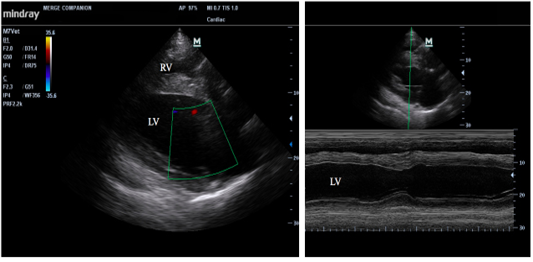

Figure 2

Echocardiographic of longitudinal image of heart (left) and M mode image of the left ventricle (right); RV = right ventricle, and LV=left ventricle.